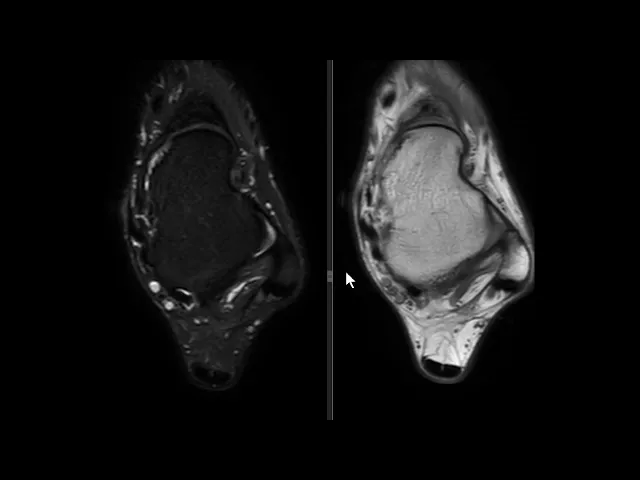

você nota nitidamente uma solução de continuidade né uma ruptura aí do ligamento talofibular anterior e edema ao seu redor existem outras alterações mas a gente vai se ater a essa alteração o ligamento talofibular posterior ele tem esse aspecto radiado né rajado é normal e o ligamento calcâneo fibular esse aqui na ponta da seta está íntegro apesar de haver edema ao redor dele então o ligamento talo fibular anterior rompeu e essa é a rotura mais frequente ligamentar no tornozelo do ligamento talofibular anterior aqui pra gente ver um comparativo com um tornozelo normal você Observe aqui a

fíbula aqui o talos e aqui você vê o ligamento talo fibular anterior aqui é uma sequência T1 e aqui uma sequência T2 com saturação de gordura você veja aí o ligamento talofibular anterior veja como ele é né em condições normais aí o ligamento talofibular anterior aqui o talo fibular posterior n talo fibular posterior ele tem esse aspecto rajado e descendo um pouco mais o calcâneo fibular fininho aqui subindo calcando fibular saio daqui e vem para cá mas o importante aqui É vermos o ligamento talo fibular anterior normal o aspecto normal dele ok Neste vídeo era